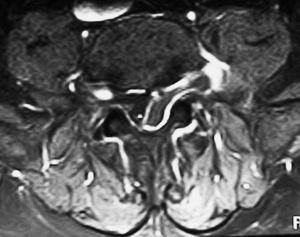

Fig. 4.--RM secuencia SE pT1 con supresión grasa espectral, tras administración de gadolinio intravenoso. Corte axial. La lesión presenta realce marginal compatible con la presencia de tejido cicatricial o de granulación perilesional. El centro no presenta realce.

Varón de 77 años con lumbociatalgia izquierda de tres meses de evolución. Se practica tomografía computarizada (TC) y resonancia magnética (RM) de columna lumbar.